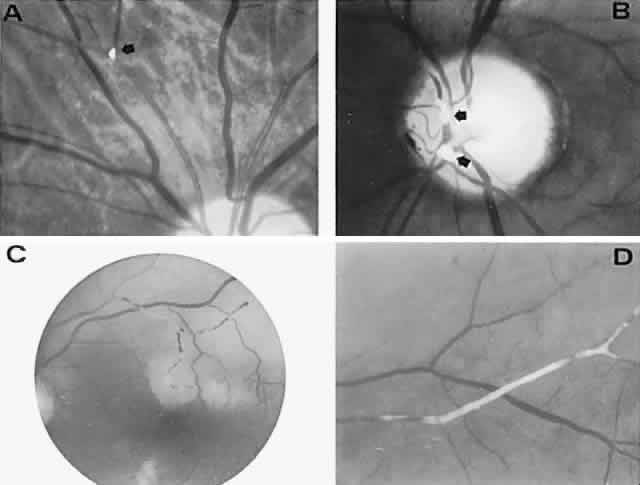

CONGENITAL HAMARTOMA SYNDROMES

The “neurophakomatoses” are a diverse group of disorders nosologically related by the presence of hamartomatous lesions, and, indeed, the term “hereditary hamartomatosis” is a more accurate description. However, whereas neurofibromatosis, tuberous sclerosis, and von Hippel-Lindau disease are transmitted with irregular dominance and considerable variation in penetrance, no hereditary basis of Sturge-Weber or angio-osteohypertrophy (Klippel-Trenaunay-Weber) syndrome has been established.

A hamartoma is a tumor of anomalous origin composed of elements normally present in the tissue in which it originates and with a limited capacity for proliferation. The following tumors may be classified as hamartomas: (1) in neurofibromatosis: optic gliomas (see Chapter 6), neurofibromas, and ganglioneuromas; (2) in tuberous sclerosis: retinal and cerebral astrocytomas, cutaneous angiofibromas (“adenoma sebaceum”), rhabdomyomas, and leiomyomas; (3) in von Hippel-Lindau disease: hemangioblastomas of the cerebellum and retina (including optic nerve head) and renal hypernephromas or cysts; (4) in Sturge-Weber disease: facial and choroidal cavernous hemangiomas and meningeal angiomatous malformations; and (5) in Klippel-Trenaunay-Weber syndrome: cutaneous nevi, visceral and limb hemangiomas, and orbitofacial venous varices.

If all disorders with neurocutaneous manifestations are considered, the term phakomatoses (Greek, phakos, “spot,” “birthmark”) is appropriate, and the catalog of “related” disorders becomes cumbersome. “The Phakomatoses,” Volume 14 of Vinken and Bruyn's Handbook of Clinical Neurology, is extraordinarily complete and serves as a source of detailed clinical descriptions of these diseases.146 Syndromes characterized by vascular hamartomas, that is, retinal-cerebellar angiomatosis (von Hippel-Lindau), and other angiomatous malformations, are discussed in Volume 2, Chapter 17.